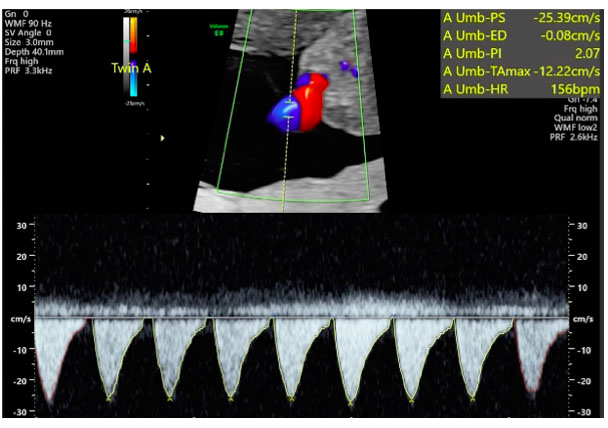

This was the first pregnancy of a 26-year old woman expecting monochorionic twins. She was first seen at 12 weeks and was followed up closely by a fetal medicine specialist with experience in the care of monochorionic twins at least fortnightly. It was obvious that Twin B’s estimated fetal weight was significantly larger than that of Twin A from 15 weeks, and this difference continued to increase as the pregnancy progressed (Figure 1). Discordances were seen in the abdominal circumferences and femur lengths. At 15 weeks gestation, the umbilical artery showed persistently positive end-diastolic flow in Twin A. This suggested that it was type I sIUGR. At 17 weeks, the Doppler studies showed persistently absent end-diastolic flow in the umbilical artery which corresponded to type II sIUGR (Figure 2). This raised concerns regarding the survival of Twin A as there was a 90% chance of deterioration of this fetus. Thus, we considered the following options for the twins: (1) expectant management with close monitoring of their arterial and venous Dopplers, (2) selective laser photocoagulation of the placental vascular, (3) cord occlusion of twin A, and (4) abortion of the whole pregnancy. With type II sIUGR diagnosis, cord occlusion of the umbilical cord of Twin A was considered to eliminate the risk of acute twin-to-twin transfusion from the bigger to the smaller twin if the smaller twin was to die in-utero. Three days later, a repeat scan, however, showed, intermittently absent and reverse end-diastolic flow of the umbilical artery (Figure 3). This changed the diagnosis to type III sIUGR. This case, thus, showed unique Doppler changes from a classification of type I to II to III sIUGR. The intermittent nature of the Doppler studies of the umbilical arteries could explain why it was first thought to be type I, then type II, and finally, type III sIUGR (Figure 4). At 32 weeks, head circumference for both Twins A and B were similar, whereas the abdominal circumferences and femur lengths for Twin A were significantly lower. The timing of the delivery was discussed with the couple and the neonatologist. As the estimated weight discordance was large at about 50% (2 and 1 kg for the Twins B and A, respectively), and the possibility of an unexpected death of the smaller twin with risk of death and morbidity to the other twin was significant, a joint decision was made to deliver the babies at 32 weeks. Corticosteroids were administered and caesarean section was performed. At delivery, the weights of Twins A and B were 1.8 and 1.2 kg, respectively, with birth weight discordance of 30%. The placenta was examined. The veins were injected with white dye and arteries injected with blue dye. Twin B’s bigger umbilical cord was centrally inserted, while that of Twin A was marginally inserted (Figure 5). The vascular equator is along the dotted line, where it shows that about 75% of the placenta belong to Twin B, while the other 25% belong to Twin A. The unequal placental sharing and the presence of an AAA (circled) validated the sIUGR type III diagnosis as these are known characteristics of this diagnosis (Figure 5). Both babies are developing well although there was mild respiratory distress syndrome (RDS) in the first few days that subsequently resolved.

Figure 3: Doppler ultrasound of Twin A’s umbilical arteries, showing intermittently reverse and absent end-diastolic flow (type III) at 17 weeks, 3 days.